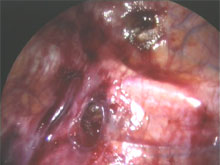

Durch zwei 5 mm große Hautschnitte in der Axelhöhle werden ein Endoskop mit Fernsehkamera und ein Clipapplikator in den Brustkorb eingeführt. Die Lunge wird durch Insufflation von Kohlendioxid vorübergehend weggedrängt. Die den Arm versorgenden Ganglien werden durch Anbringen eines Metallclips komprimiert. Dadurch wird die Nervenleitung unterbrochen. Bei Operation wegen Hyperhidrosis wird lediglich das vierte Thorakalganglion geclipt, um Nebenwirkungen wie kompensatorisches Schwitzen an anderen Körperregionen möglichst gering zu halten. Der Eingriff dauert nur wenige Minuten und wird simultan an beiden Armen durchgeführt.